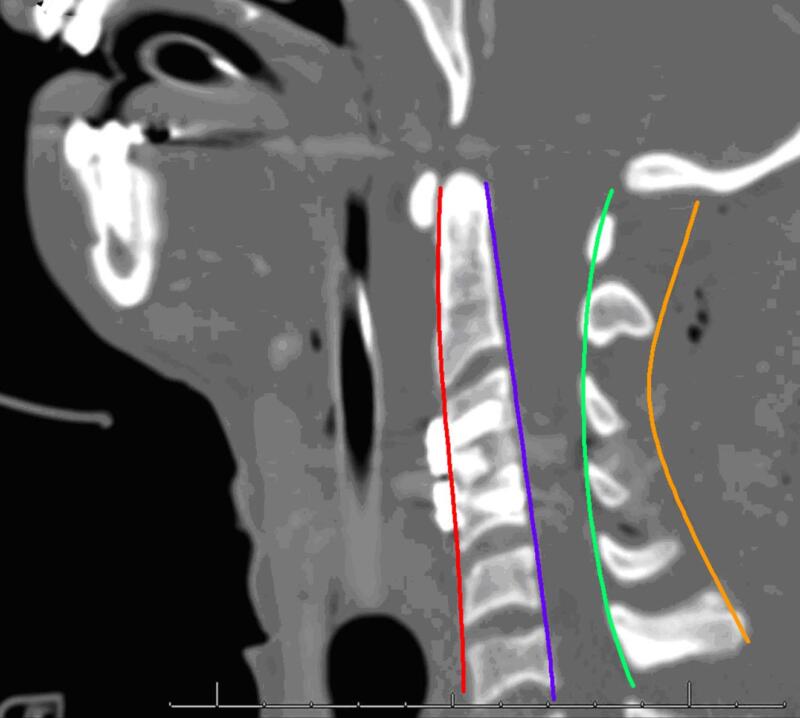

Xét nghiệm chẩn đoán tiêu biểu được chỉ định đầu tiên ở BN có triệu chứng bệnh lý tủy cổ là MRI. MRI cung cấp chi tiết tuyệt vời về mức độ hẹp ống sống, bệnh lý đĩa đệm, phì đại dây chằng, và những thay đổi nội tại của tủy sống. Đường kính bình thường trước sau của tủy sống trên MRI là 13-15mm, nếu <13mm thì được coi là hẹp ống sống. MRI cũng có thể giúp phân biệt bệnh lý tủy cổ do thoái hóa với các bệnh lý khác như u tủy cổ, bệnh lý thoái hóa myelin, hoặc nhiễm trùng. Phim CT scan và Xquang gập/duỗi có thể có ích cho việc đánh giá cấu trúc giải phẫu xương và sự thẳng hàng của cột sống cổ, đặc biệt trong trường hợp xem xét chỉ định phẫu thuật.

Hình 15. Xquang giải phẫu đốt sống: Dựa vào các đường cong sinh lý là phương pháp nhanh chóng để đánh giá tình trạng dịch chuyển và mất vững tiềm ẩn.